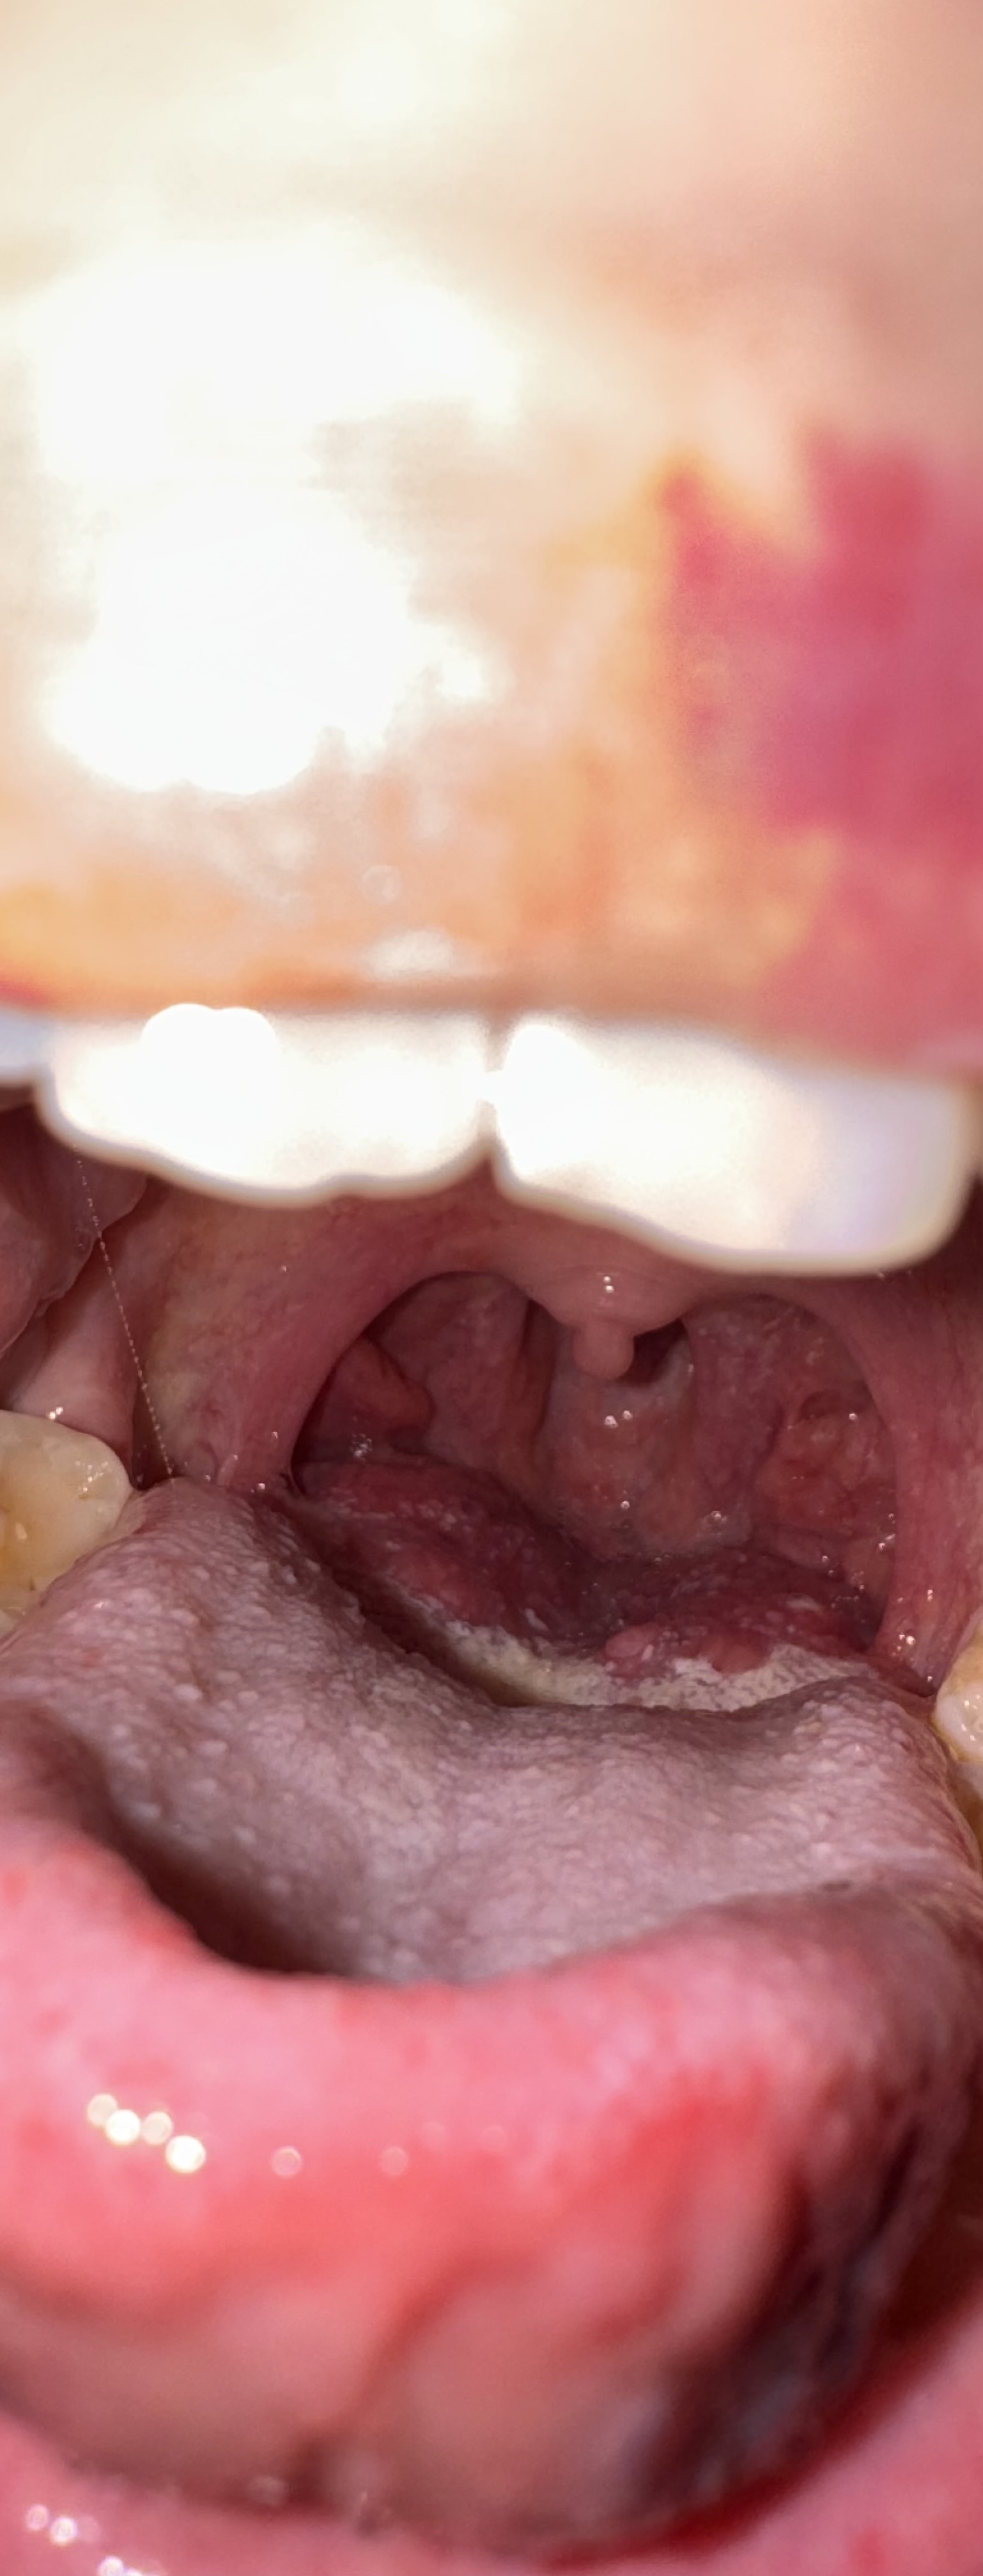

ich habe ein Engegefühl/ Kloßgefühl im Hals. Ich habe gesehen das mein Zungengrund geschwollen ist. Jetzt habe ich totale Angst.